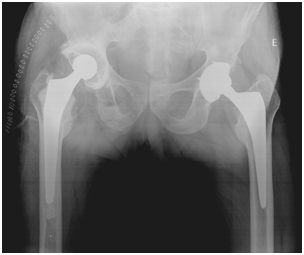

In 2004 while preparing for right THA, it was identified thrombosed aneurysm of the right popliteal artery in need of carrying out femoral-popliteal bypass. Because of this major vascular event, the right hip arthroplasty has been successively delayed until 2012. At this time, and after balancing the risks and benefits, was decided to perform a right cemented THA. The surgery and the postoperative elapsed normally without any adverse vascular, orthopedic or neurologic events (Figure 2).

Figure 2 Post-operative X-Ray.